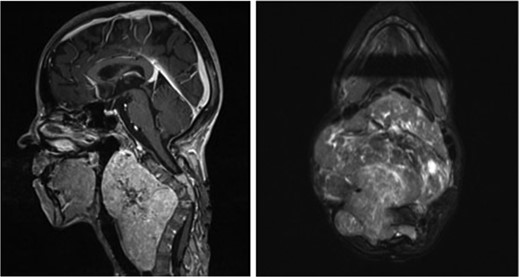

Sagittal (left) and axial (right) T1-weighted contrast-enhanced magnetic resonance images before the second surgery, showed increased size of the extraspinal component of the tumor, with kyphotic deformity of the cervical spine.